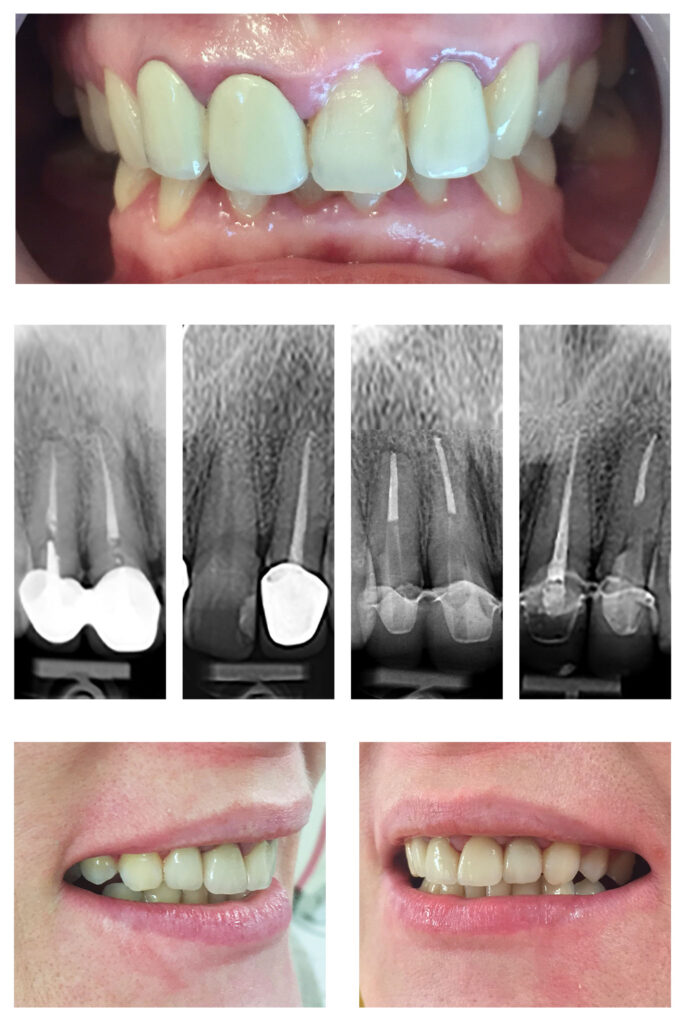

Coroniță zirconiu pe incisivul central cu integrarea estetică

Protezarea fixă a incisivului central superior cu lucrarea din zirconiu stratificat

Extruzia ortodontică a dinților cu distrucție subgingivală accentuată salvează unii dinți de la extracție…pentru că dintele natural este cel mai bun implant. Săgețile evidențiază cât de multă extruzie am reușit să obținem în câteva luni.